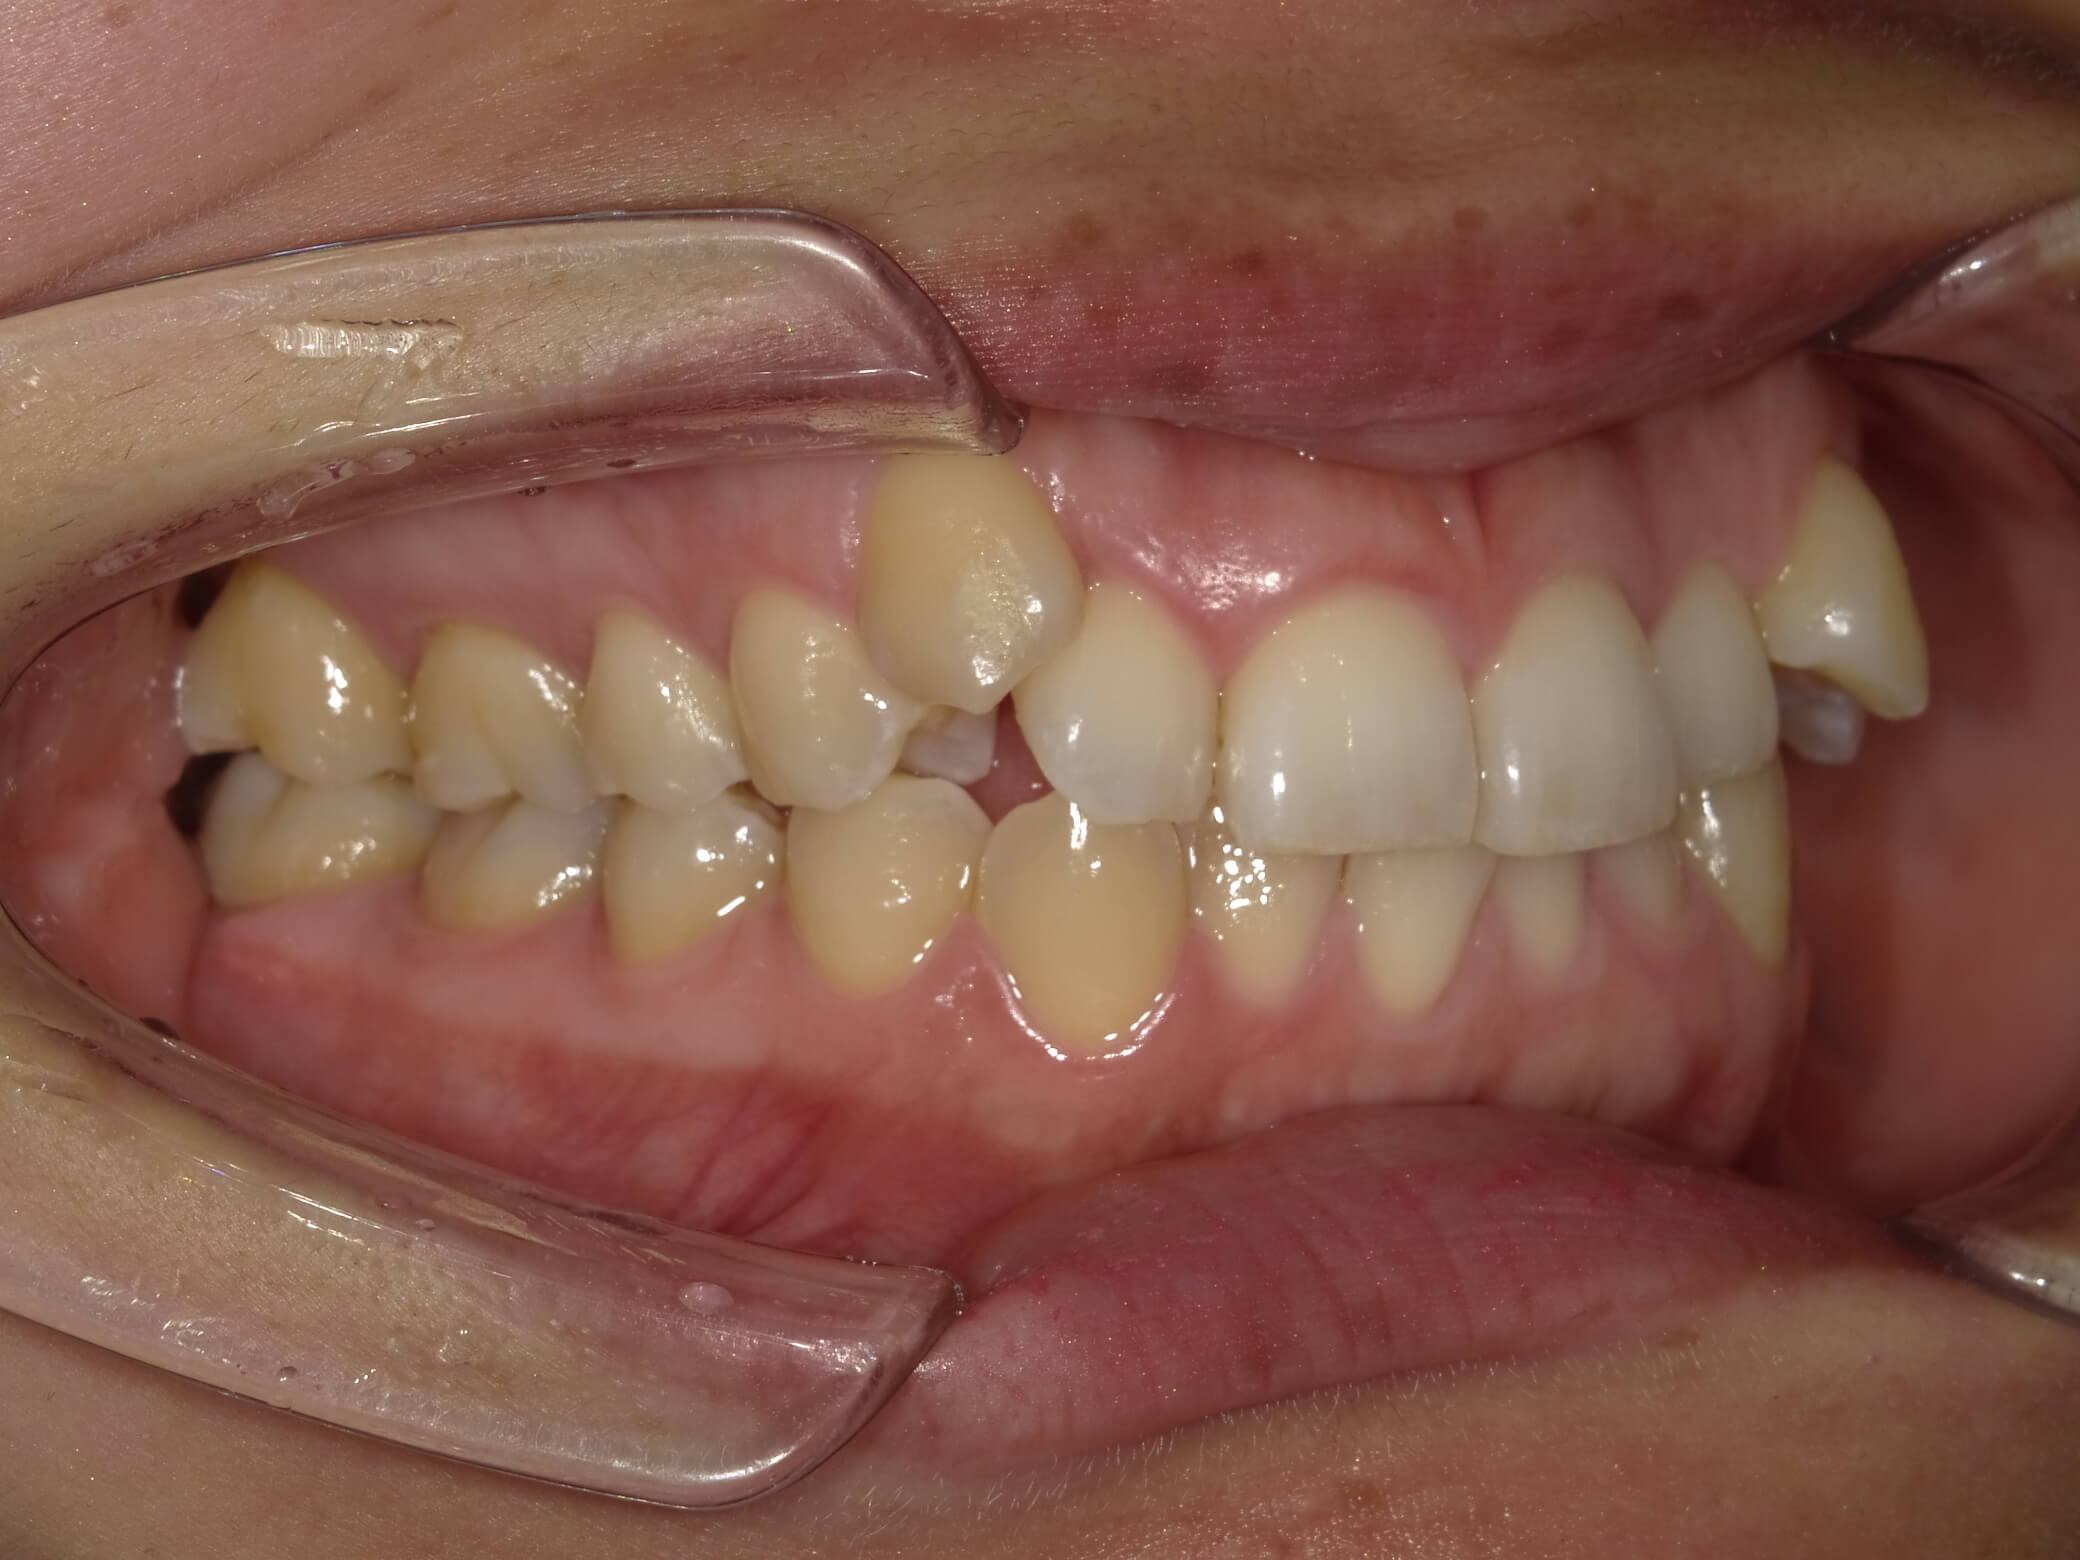

• 治療前